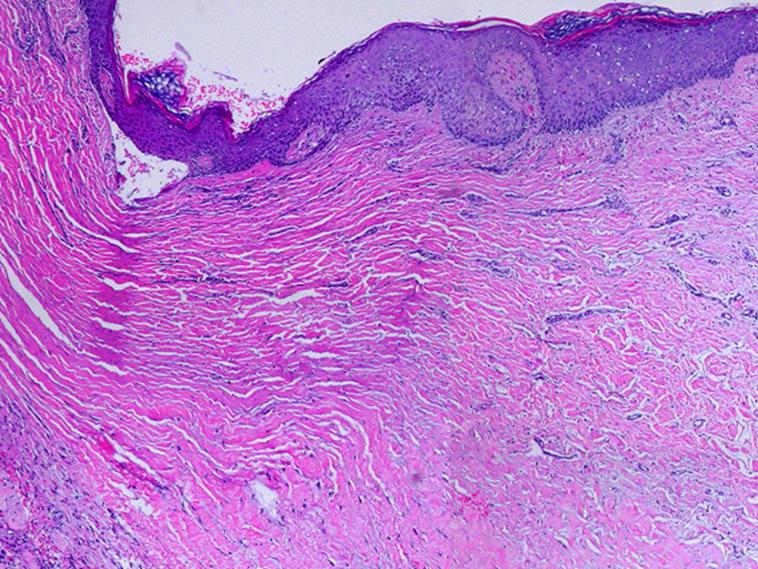

SLIDE SUMMARY:  This is a view of regenerated Integra side-by-side with normal wound healing.  Each half is completely normal and healthy, but the differences are profound - normal wound module versus induced dermatogenesis.

------------------------------------------------------------------------------------------------------------------------------------

This is a slide showing two distinctly different yet entirely normal events.  On the left is a normal wound module.  On the right is normal Integra.  An original biopsy was taken a week earlier.  The biopsy site, now a normal open wound, developed normal granulation tissue.  The new biopsy was centered on the boundary.  Each half of the image is a completely normal and paradigm demonstration of their own events - normal post-inflammatory wound module, and normal Integra histogenesis.  Absent the matrix, cells follow their normal healing program.  In the presence of the GAG matrix, inflammation-repair is suppressed, and embryonic histogenesis is induced.  Cells, all having the same genotype, remain pluripotential, and can be induced to one reactive program or another depending on inputs.  The histogenesis response never occurs in normal post-parturitional injury and healing, but it can obviously be invoked with the right trigger.